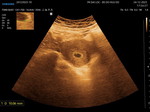

Các món cho em hỏi em bầu 12 tuần mà cổ họng em cứ bị khô vs khó chịu .

Mon nào bít cách gì hay chỉ em vs ạ